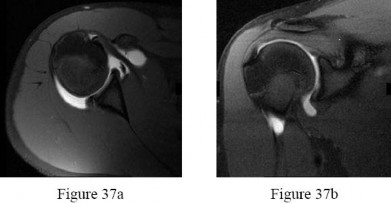

A 24-year-old professional baseball pitcher presents with vague anterior shoulder pain and a 'dead arm' sensation. MR arthrogram reveals a bucket-handle tear of the superior labrum that extends into the long head of the biceps tendon, resulting in an unstable biceps anchor. According to the Snyder classification, what type of SLAP tear is this?

The Snyder classification of SLAP (Superior Labrum Anterior to Posterior) tears: Type I is fraying of the superior labrum with an intact biceps anchor. Type II is a detachment of the superior labrum and biceps anchor from the superior glenoid. Type III is a bucket-handle tear of the superior labrum with an intact biceps anchor. Type IV is a bucket-handle tear of the superior labrum that extends into the biceps tendon, resulting in instability of the biceps anchor.